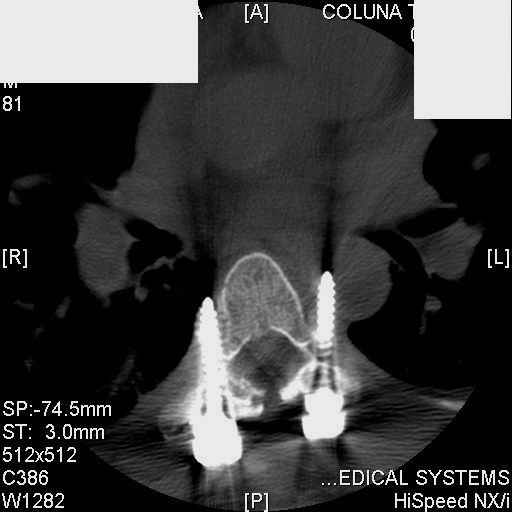

Interesting case. Findings on CT: all four pedicle screws have been placed improperly inthat they miss the vertebral bodies. In addition, the screws on the left side are impingingon the decending thoracic aorta. What I do NOT know is the nature of the original injury, orwhether or not that injury has resolved. I would recommend removal of the hardware. I don'tthink it's a good idea to leave those screws where they are. If the original fracture ishealed, nothing else needs to be done.

dear Mark, all the details are not yet available but the patient is coming to see us foradvice. We probably will see him in the early new year. i thought that the 4th picture showedthe screw to enter the aorta? He is a victim of a motor vehicle crash and thoracic vertebralfracture which appears healed. He was posteriorly decompressed and this device inserted. asyou say there isno evidenece that any of the fixation enters the bodies via the pediclesistead they have passed thru and their end are no where near where they ought to be. If I amcorrect (I would prefer not to be) the aortic intima has been breached by the screw. When thetime comes to take the screw out I thought we should have control of the aorta.What do you think?

Tom: I strongly doubt that the aorta is involved. When these screws are put in, they firstput in a probe, then a tap, then the screw. If the aorta was punctured, they would have knownat the time. You might call the original surgeon (if in fact he is a real doctor) and get hisfeedback. The additional morbidity of a prophylactic thoracotomy would be a higher pricethan I would be willing to subject my patient to. Besides, it would be exceptionallydifficult to control the aorta at this point, especially if you tried to specifically getenough control to be able to put sutures in the back wall. Of course, difficulty of doingsomething isn't necessary a reason not to do it if you think it is necessary. I just think itis highly unlikely that the aorta is injured. I showed the case to both a thoracic surgeon anda neurosurgeon. The thoracic surgeon suggested getting an arteriogram to see if the aorta isinvolved. The neurosurgeon agreed that the hardware should be removed.

Mark Thank you. He is scheduled for a angio prior to transfer here. I keep going back to lookat that fourth image and although it is tough to believe the wall of the aorta seems toencompass the distal 1/2 of the screw. I have come to anticipate mal postion of screws thathave been inserted in hospitals that perhaps may not have the highest quality of equipment,including the human and radiological components. That having been said this case seems tosurpass the usual... one screw out of place or screwed into a disc etc. BTW I am notsuggesting that the screw was placed directly into the aorta but that moviment, pulse actionetc may have caused it to transgress the normal anatomical bounds without evident hemorrhage.

Подошли ангиограммы... Наслаждайтесь...

травматический обратный дивертикул аорты!